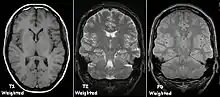

T1 and T2

Each tissue returns to its equilibrium state after excitation by the independent relaxation processes of T1 (spin-lattice; that is, magnetization in the same direction as the static magnetic field) and T2 (spin-spin; transverse to the static magnetic field). To create a T1-weighted image, magnetization is allowed to recover before measuring the MR signal by changing the repetition time (TR). This image weighting is useful for assessing the cerebral cortex, identifying fatty tissue, characterizing focal liver lesions, and in general, obtaining morphological information, as well as for post-contrast imaging. To create a T2-weighted image, magnetization is allowed to decay before measuring the MR signal by changing the echo time (TE). This image weighting is useful for detecting edema and inflammation, revealing white matter lesions, and assessing zonal anatomy in the prostate and uterus.

The standard display of MR images is to represent fluid characteristics in black-and-white images, where different tissues turn out as follows: